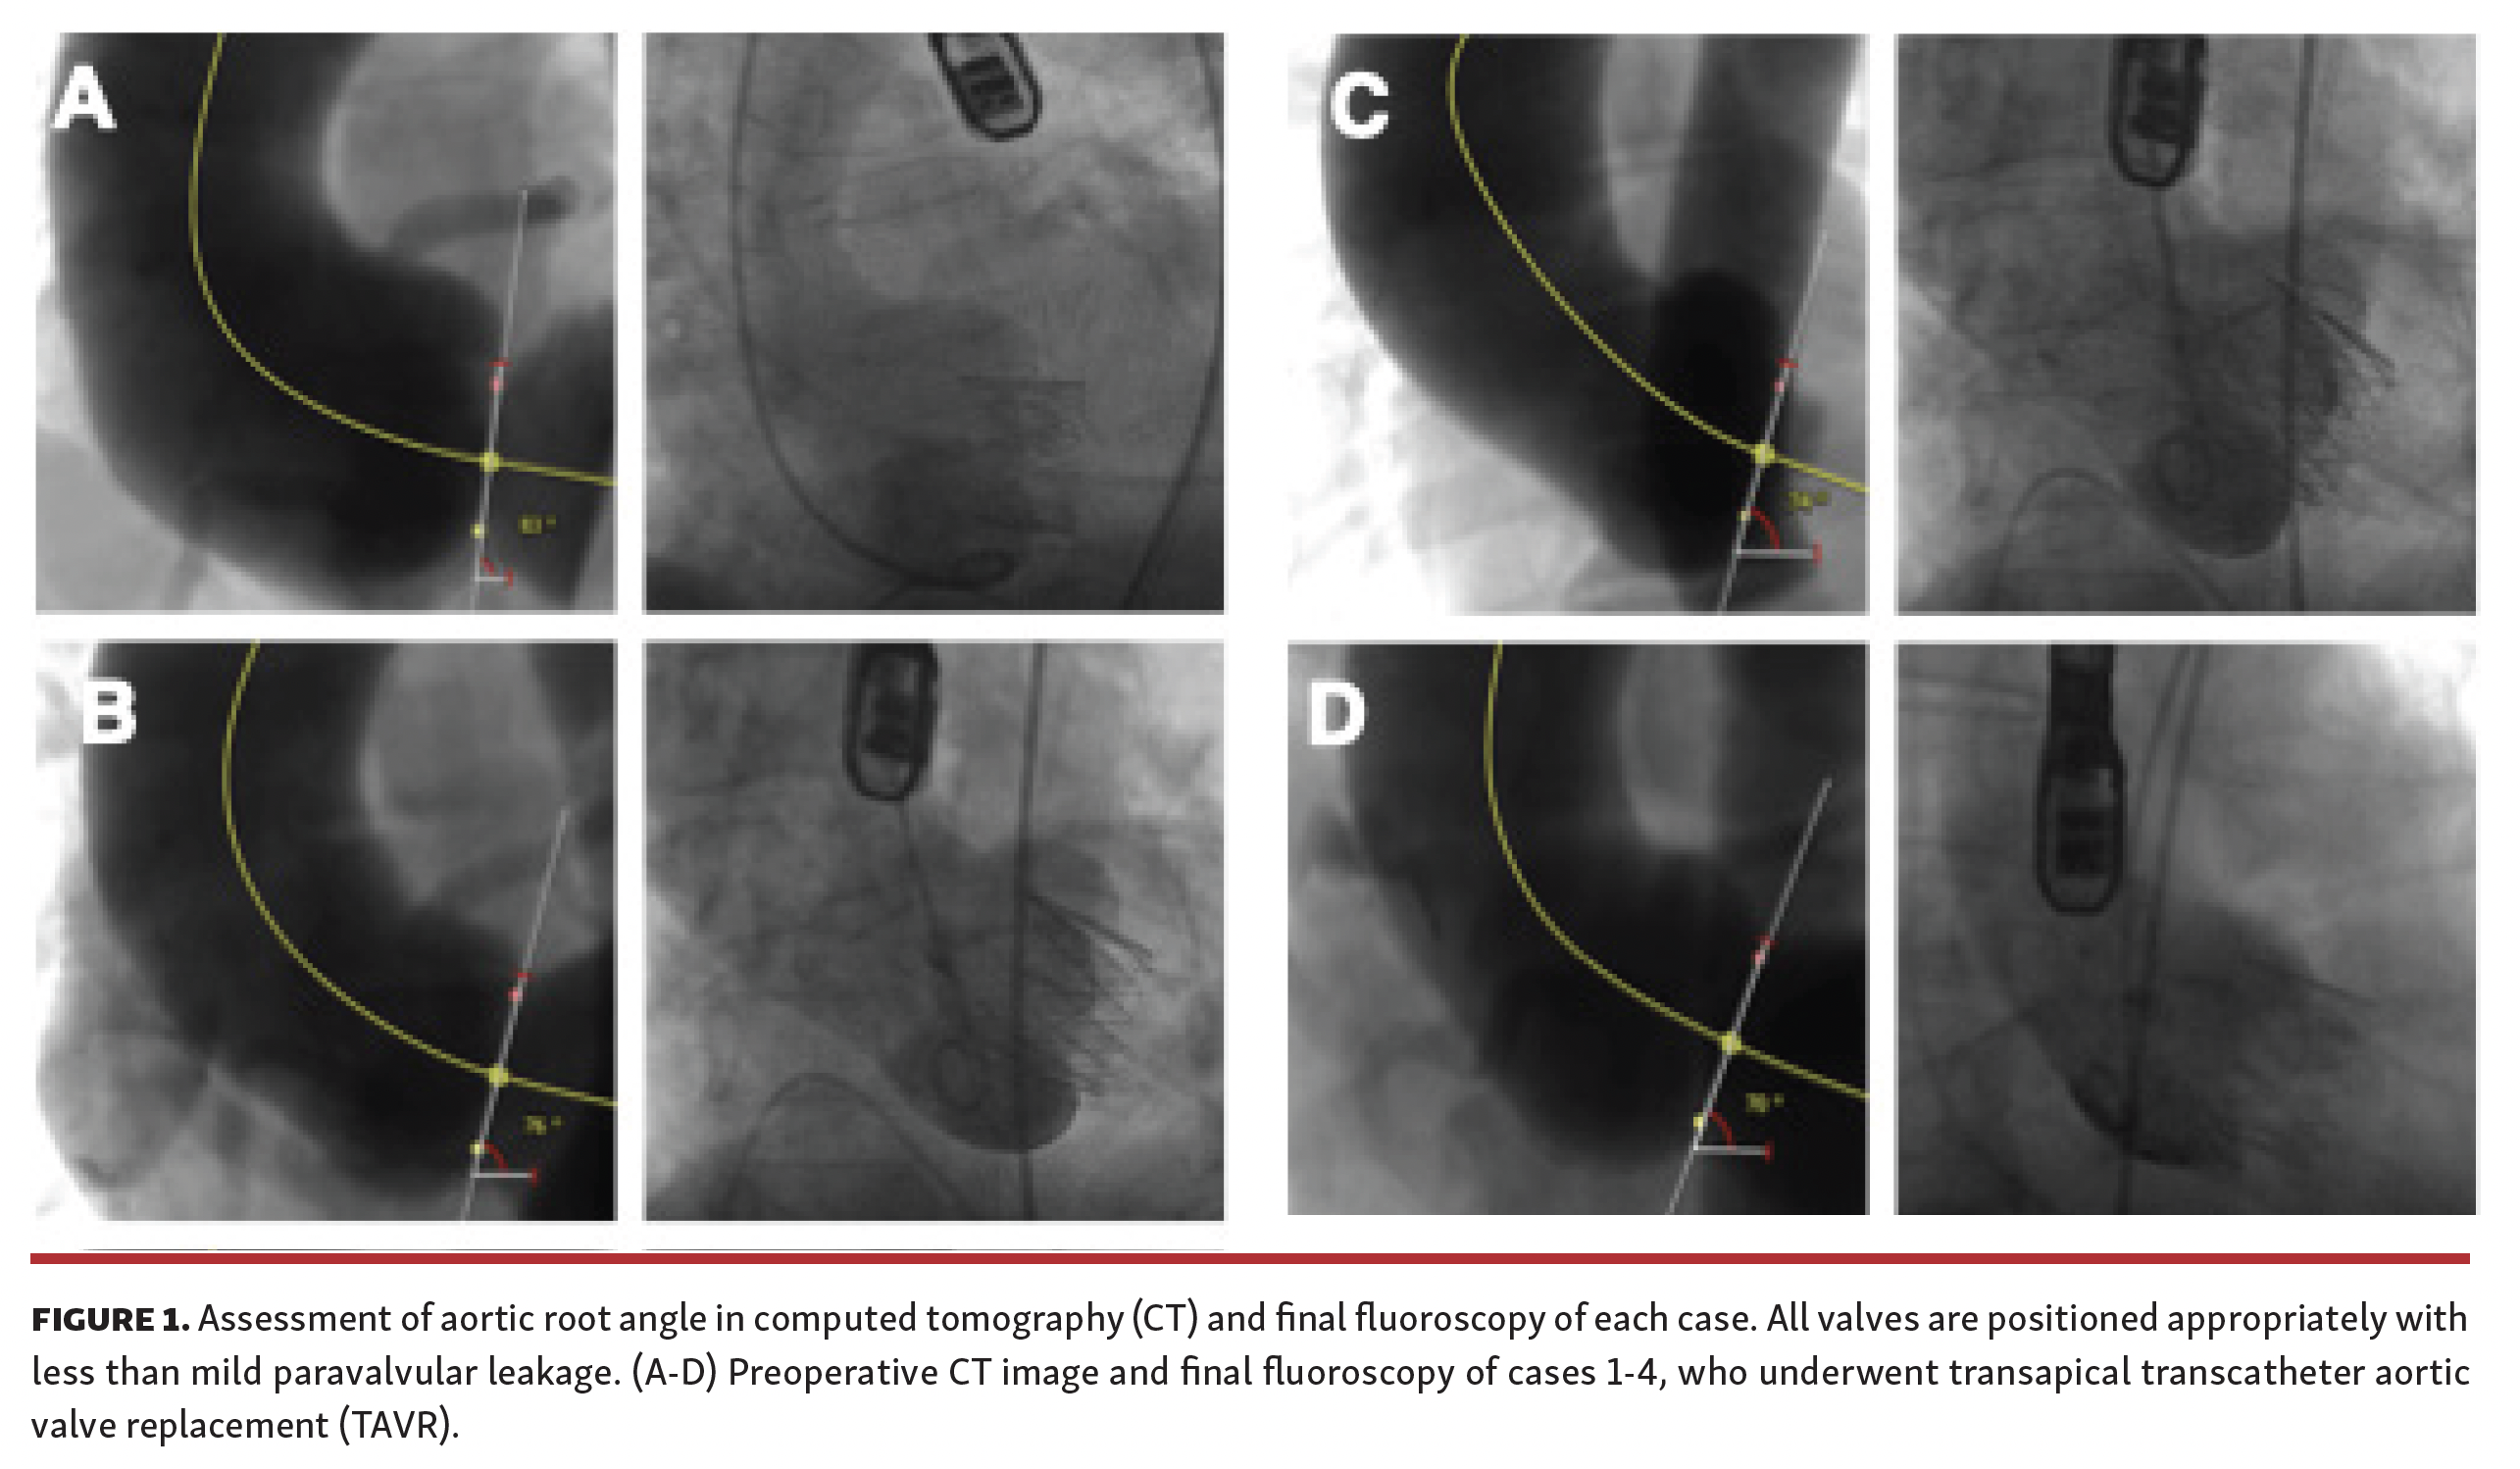

Transcatheter aortic valve replacement (TAVR) is not the preferred therapy for pure aortic regurgitation (AR). Extremely horizontal aorta (aorta root angle ≥70°) is regarded as an “off-label” use in self-expanding TAVR. This case series enrolled 7 consecutive pure AR patients who had extremely horizontal aorta and underwent self-expanding TAVR from the TORCH registry (NCT02803294). The mean age was 74.1 ± 8.3 years and the Society of Thoracic Surgeons (STS) score was 3.8 ± 1.5%. All patients lacked calcification at the aortic root. Transapical TAVR with a J-valve (Jiecheng) was performed in 5 patients and transfemoral TAVR with a Venus-A valve (Medtech) was performed in 2 patients (Figure 1 Part 1 and Figure 1 Part 2).

Case 1 received permanent pacemaker implantation and suffered a non-disabling stroke, while case 4 and case 5 suffered major bleeding during 30-day follow-up. Detailed aortic angulation measurement and fluoroscopy during the procedure are shown in Figure 1 Part 1 and Figure 1 Part 2. Nevertheless, procedural success was achieved in all patients according to Valve Academic Research Consortium-2 definitions and no patients were at New York Heart Association class III/IV at 30 days. To the best of our knowledge, this is the first study to report successful self-expanding TAVR for pure AR with extremely horizontal aorta, revealing the feasibility of both transapical and transfemoral TAVR in this challenging population.